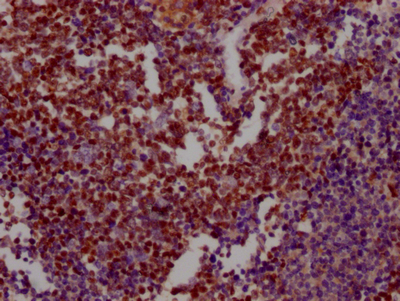

IHC image of CSB-RA276627A0HU diluted at 1:100 and staining in paraffin-embedded human breast cancer performed on a Leica BondTM system. After dewaxing and hydration, antigen retrieval was mediated by high pressure in a citrate buffer (pH 6.0). Section was blocked with 10% normal goat serum 30min at RT. Then primary antibody (1% BSA) was incubated at 4℃ overnight. The primary is detected by a Goat anti-rabbit IgG polymer labeled by HRP and visualized using 0.05% DAB.

IHC image of CSB-RA276627A0HU diluted at 1:100 and staining in paraffin-embedded human lung cancer performed on a Leica BondTM system. After dewaxing and hydration, antigen retrieval was mediated by high pressure in a citrate buffer (pH 6.0). Section was blocked with 10% normal goat serum 30min at RT. Then primary antibody (1% BSA) was incubated at 4℃ overnight. The primary is detected by a Goat anti-rabbit IgG polymer labeled by HRP and visualized using 0.05% DAB.